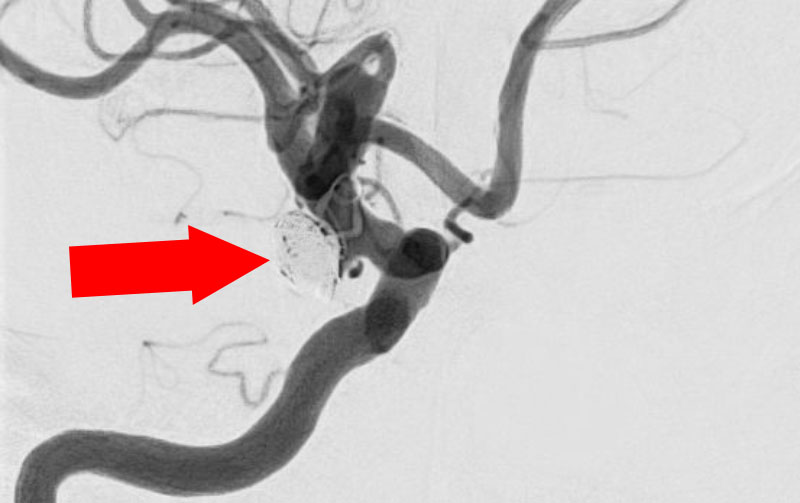

No.1618 手術中